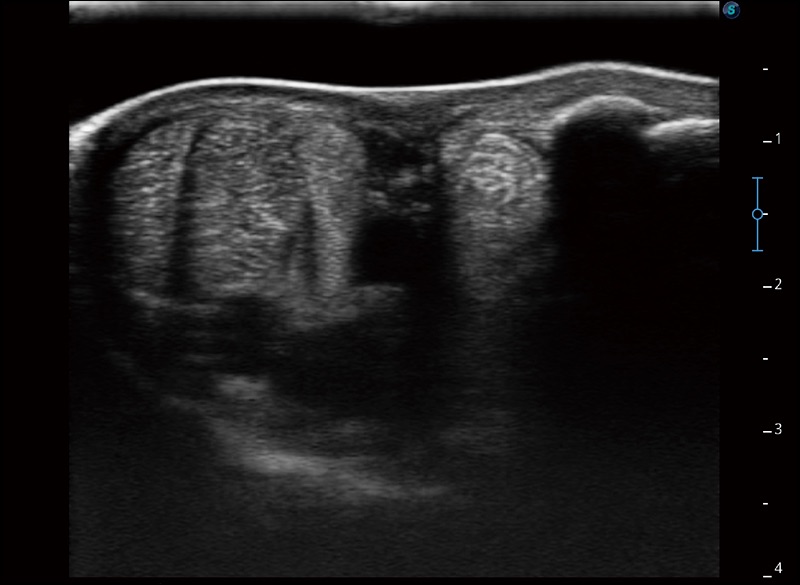

任意波束合成技术

在不牺牲时间分辨率的情况下提供出色的图像

空间复合成像

优化不同角度的图像

扩展成像

支持线阵和凸阵探头,一键操作即可获得更宽的图像视野

实时宽景成像

可实时观察感兴趣区域和病变位置

穿刺针增强

高清显示穿刺进针情况